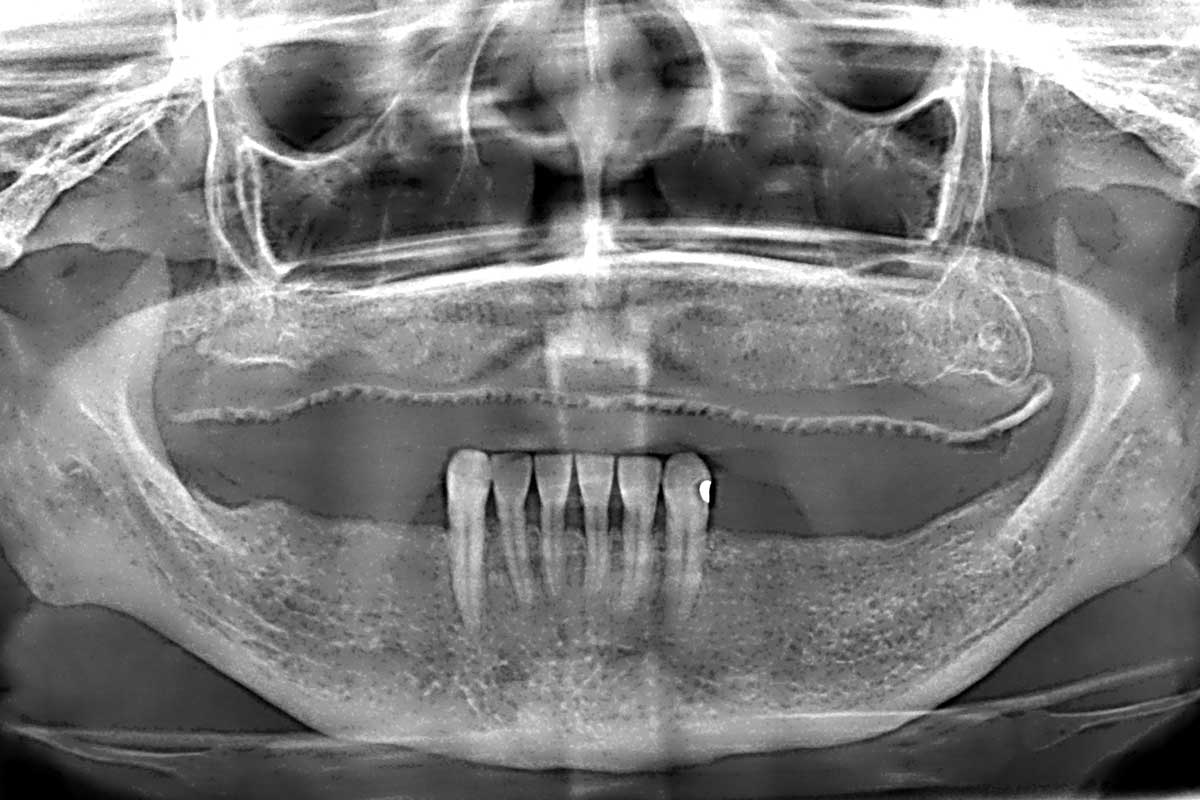

Initial x-ray showing bone loss around implants placed 5 years ago in another dental clinic